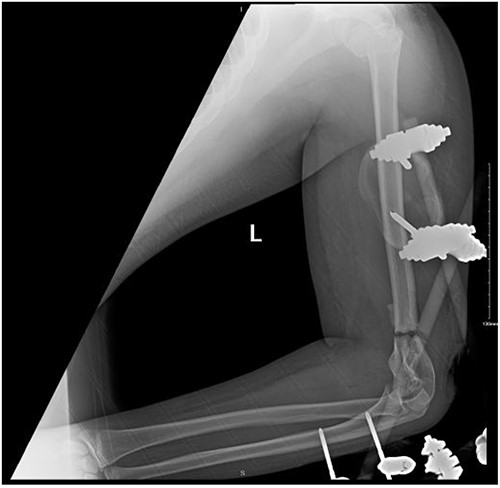

A 14-year-old boy with unknown medical and surgical history was brought by the emergency medical services to the emergency department as a case of multiple trauma after a MVA. Upon arrival, primary and secondary surveys were conducted, and management followed accordingly. After stabilization, all related specialties were involved in case management. Multiple fractures were detected, including left mandible, acetabular, open femur, and humerus fractures, as well as a comminuted pelvic fracture. The humerus fractures involved the proximal and distal area, as shown in Fig. 1.

Anteroposterior (AP) view of the left humerus and elbow pre-operative.